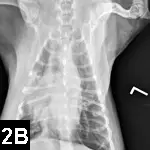

Radiography and abdominal ultrasonography

• Survey radiography is indicated for pulmonary, pleural, or abdominal hemorrhage (Figures 2A and B).

Figure 2A. Lateral thoracic radiograph of a Welsh corgi (9 years of age) following ingestion of an anticoagulant rodenticide at least 3 days before presentation. Note the mixed pattern of alveolar infiltrates and scant pleural effusion (hemorrhage).

Figure 2B. VD radiograph of the patient. Alveolar pattern in the right cranial and middle lung lobes represents one of the radiographic manifestations of pulmonary hemorrhage.